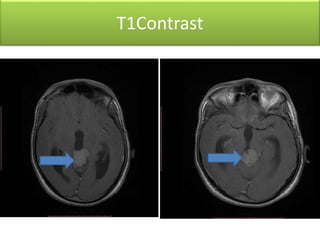

T1Contrast

• Soft tissue mass lesion measureing2.9 X 2.7 X 2.7 cm

• Hypointense T1,hyperintense T2 / FLAIR signal &

homogenous post-contrast enhancement

• Lesion is compressing the superior portion of the cerebral

aqueduct with moderate supratentorial hydrocephalus